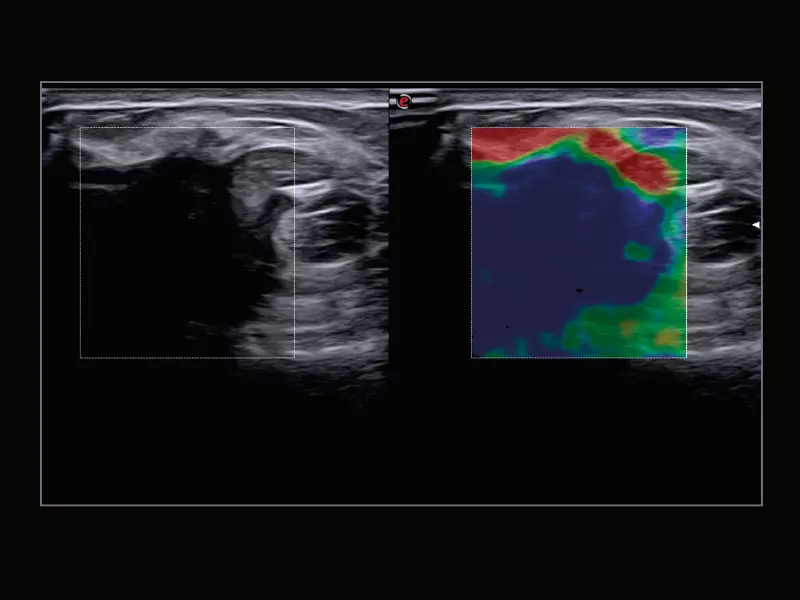

MyLab™9 Platform - Dual ElaXto characterization on breast lesion

MyLab™9 Platform - Dual ElaXto characterization on breast lesion

MyLab™X8 Platform - Lesion with ElaXto

MyLab™X8 Platform - Lesion with ElaXto

MyLab™Omega - Dual ElaXto on breast cyst

MyLab™Omega - Dual ElaXto on breast cyst